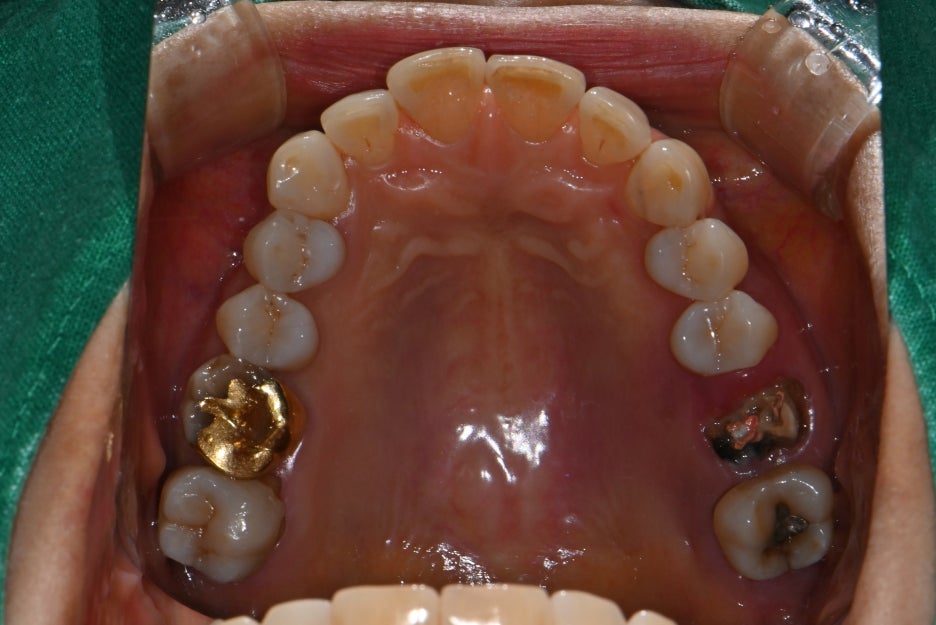

파노라마 엑스레이와 구강내 사진을 통해 확인한 결과,

왼쪽 위 두 개의 어금니가 파절 및 결손 상태

주변 치조골은 비교적 건강하여 뼈이식이

최소화된 상태에서도 임플란트 식립 가능

이라는 진단을 내렸습니다.

치료 전 후 사진